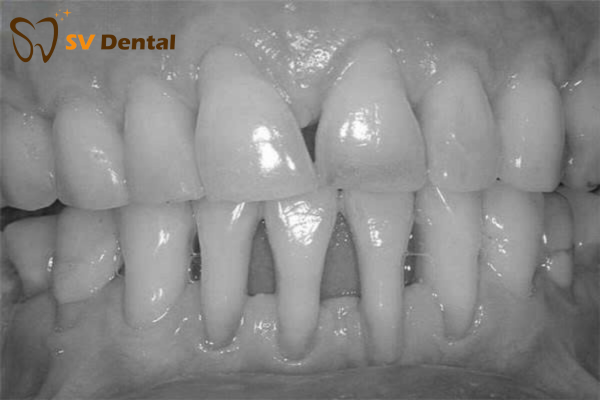

Hậu quả của tụt lợi nếu không điều trị

Mất men răng – lộ ngà → ê buốt khi ăn uống.

Mòn cổ răng – nhồi nhét thức ăn → viêm nặng hơn.

Răng trông dài – mất thẩm mỹ → kém tự tin khi giao tiếp.